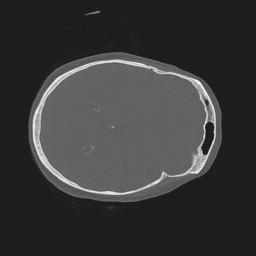

Model-based treatment planning for transcranial ultrasound therapy typically involves mapping the acoustic properties of the skull from an x-ray computed tomography (CT) image of the head. Here, three methods for generating pseudo-CT images from magnetic resonance (MR) images were compared as an alternative to CT. A convolutional neural network (U-Net) was trained on paired MR-CT images to generate pseudo-CT images from either T1-weighted or zero-echo time (ZTE) MR images (denoted tCT and zCT, respectively). A direct mapping from ZTE to pseudo-CT was also implemented (denoted cCT). When comparing the pseudo-CT and ground truth CT images for the test set, the mean absolute error was 133, 83, and 145 Hounsfield units (HU) across the whole head, and 398, 222, and 336 HU within the skull for the tCT, zCT, and cCT images, respectively. Ultrasound simulations were also performed using the generated pseudo-CT images and compared to simulations based on CT. An annular array transducer was used targeting the visual or motor cortex. The mean differences in the simulated focal pressure, focal position, and focal volume were 9.9%, 1.5 mm, and 15.1% for simulations based on the tCT images, 5.7%, 0.6 mm, and 5.7% for the zCT, and 6.7%, 0.9 mm, and 12.1% for the cCT. The improved results for images mapped from ZTE highlight the advantage of using imaging sequences which improve contrast of the skull bone. Overall, these results demonstrate that acoustic simulations based on MR images can give comparable accuracy to those based on CT.